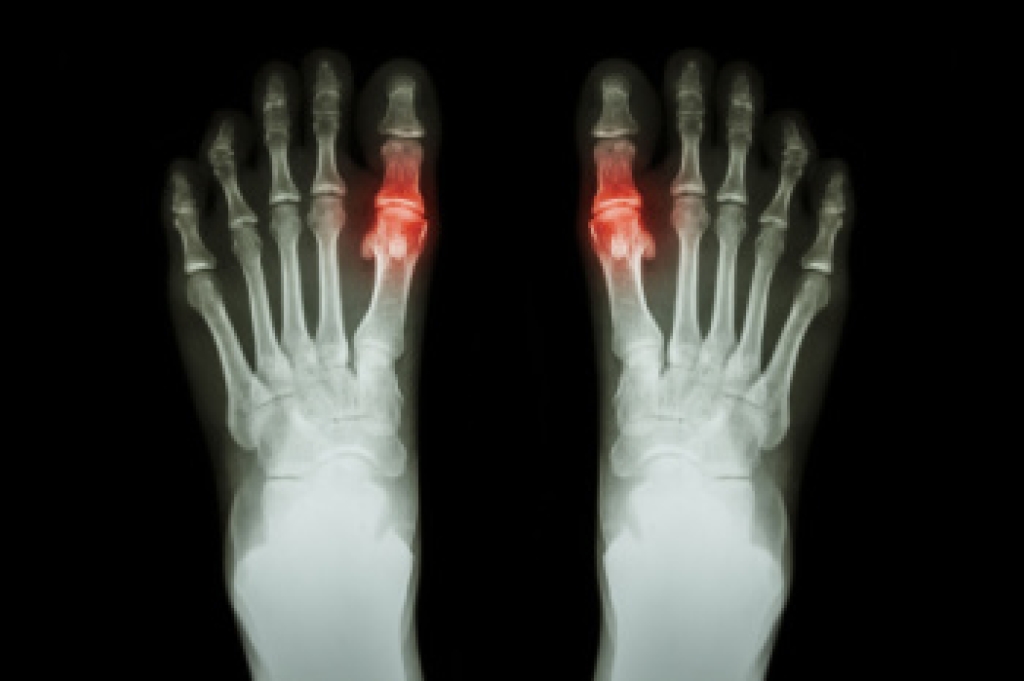

Stress fractures occur in the foot and ankle when muscles in these areas weaken from too much or too little use. The feet and ankles then lose support when walking or running from the impact of the ground. Since there is no protection, the bones receive the full impact of each step. Stress on the feet can cause cracks to form in the bones, thus creating stress fractures.

Pain from the fractures occur in the area of the fractures and can be constant or intermittent. It will often cause sharp or dull pain with swelling and tenderness. Engaging in any kind of activity which involves high impact will aggravate pain.